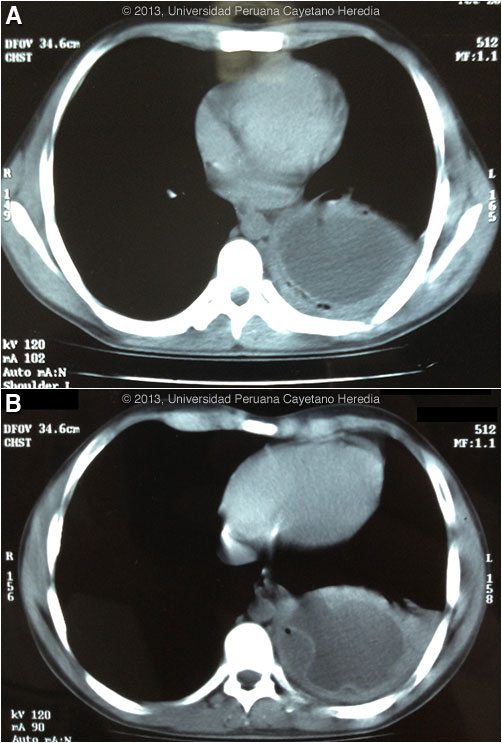

Epidemiology: Born and lives in Huánuco in the highlands where he works in construction. Grew up on a farm with various animals including dogs, sheep, cows, and pigs. No travel. No known TB exposure. No ill contacts. Physical Examination: Afebrile. Normal examination except for decreased breath sounds and dullness in the left base. Laboratory Results: Hb 14.0, WBC 17,000 with 77 PMNs, no monocytes, no eosinophils. Normal renal and hepatic function. HIV negative. Chest CT scan is shown in Images A & B.

![]() Discussion: The fluid-filled pulmonary cyst on CT scan with detached membrane [Image B] is diagnostic of hydatid disease without any further serology (usually a western blot) or diagnostic procedure. The air between the detached parasite membrane and the cavity wall is indicative of erosion into a bronchus. Serology is usually positive with solitary hepatic cysts but sensitivity drops below 50% with solitary pulmonary cysts even when the cyst is large such as this. Treatment of pulmonary hydatid is surgical and most surgeons will not operate if pre-operative albendazole has been given as this softens the cyst wall somewhat. The patient underwent a left hemi-lobectomy. Image C shows the resected lung with the large cavity lined by the hydatid membanes. Image D shows the acellular lamellated white parasite membrane stripped away from the cyst cavity. The forceps are holding the inner germinal membrane of the cyst, which is the layer that is alive and contains the cells that continuously produce new tapeworm scoleces. Previous pulmonary hydatid cases we have shown are Gorgas Cases 2005-10 and 2011-05. In adults the expectoration of salty-tasting fluid with or without pieces of white membranous material is highly characteristic of a fistula or frank rupture of a cyst into a bronchus, but this patient did not describe this. Sputum production and fever may have been due to a small fistula with resulting bacterial superinfection. He was treated with ceftriaxone on admission. Human hydatid disease secondary to Echinococcus granulosus is caused by the larval form of this dog tapeworm. Humans ingest the tapeworm eggs in environments contaminated by canine feces and become accidental intermediate hosts. This patient had ongoing exposure to dogs during his whole life. Sheep are the normal intermediate hosts. In general, disease is diagnosed in adulthood as larval cysts expand slowly over years or decades, becoming symptomatic as they impinge on other structures by virtue of their size. The cysts contain hundreds of viable protoscoleces capable of becoming adult tapeworms upon ingestion by a definitive host such as the dog. The internal germinal membrane lining the cyst produces new protoscoleces on an ongoing basis. Each protoscolex is capable of becoming a new daughter cyst should the original cyst rupture or be ruptured. Cystic hydatid disease due to E. granulosis is common in sheep and cattle raising areas worldwide. Most primary infections involve a single cyst. In adults, 65% of solitary cysts are found in liver, 25% in lung and the rest in a wide variety of other organs including kidney, spleen, heart, bone and brain. In patients with a pulmonary cyst, approximately 18% will also have a hepatic cyst. The patient has not pursued abdominal imaging at this point. Surgery may involve excision of the cyst or resection of the cyst and the immediate surrounding parenchyma. Despite the lack of consensus, the currently most accepted surgical treatment for lung hydatic is complete excision using parenchyma-preserving methods, such as cystostomy, intact cyst enucleation or removal after needle aspiration preserving as much lung parenchyma as possible. Resection techniques such as pneumonectomy, segmentectomy should be reserved to cysts involving whole hemithorax or the whole segment respectively; and lobectomy generally should be performed only in large abscessed cysts. Most surgeons use pads soaked in hypertonic saline to protect the operatory field from spillage and subsequent seeding of new cysts. Albendazole is the therapy of choice for intact cysts that are not operable, such as when there are multiple or disseminated cysts. A trial of continuous albendazole may also be considered for solitary cysts that are less than about 5 cm. Response is generally slow. Albendazole should be immediately instituted in ruptures whether they be spontaneous, post-traumatic or the result of a surgical accident. Praziquantel is the most potent scolicidal drug and is the drug of choice for all adult tapeworms. In hydatid disease, praziquantel is unlike albendazole and does not penetrate the cyst wall or produce measurable concentrations in cyst fluid. Praziquantel is also ineffective against the germinal membrane of cysts, but is able to reliably and quickly kill free protoscoleces [Acta Trop. 2009 Aug;111(2):95-101]. Thus, praziquantel is useful as an acute therapy when a cyst ruptures (spontaneously, or intra-operatively due to surgical mishap) and scoleces are lying free before encysting again. A recent international consensus document [Acta Trop. 2010 Apr;114(1):1-16] also recommends routine pre-operative praziquantel/albendazole therapy for liver cysts in case of surgical spillage. Combined praziquantel and albendazole for medical therapy of liver or lung hydatid has been reported in several small uncontrolled series and experimental protocols examining combination therapy using are underway in several places.